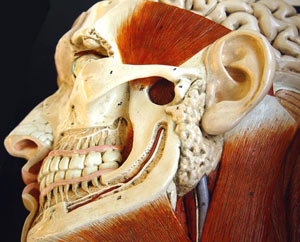

ستون فقرات ساختمان پیچیده ای است که ازعضله، تاندون، رباط واستخوان های متعددی ساخته شده است. این ساختمان به گونه ای طراحی شده است که بتواند به جلو، عقب، چپ و راست خم شود و وزن بدن را تحمل کند .